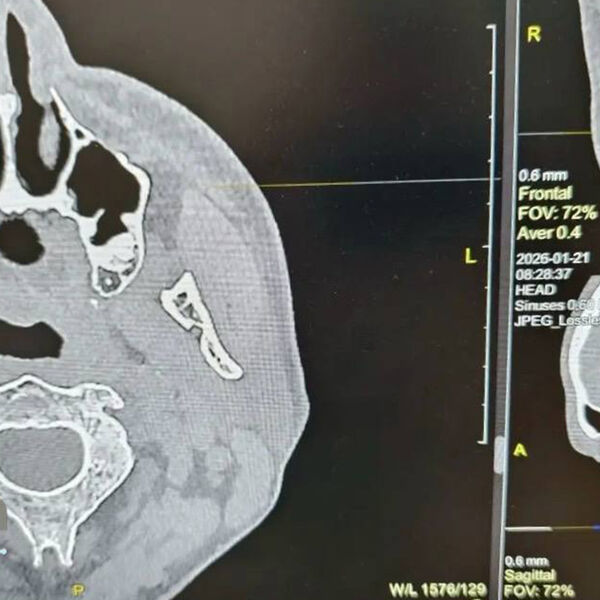

Диагностика показала, что в правой носовой пазухе мужчины находится зуб. Мужчина вспомнил, что незадолго до этого удалял зуб у стоматолога. Как пояснили врачи, во время процедуры могла нарушиться целостность костной перегородки между зубным рядом и пазухой, из-за чего зуб или его фрагмент сместились внутрь.